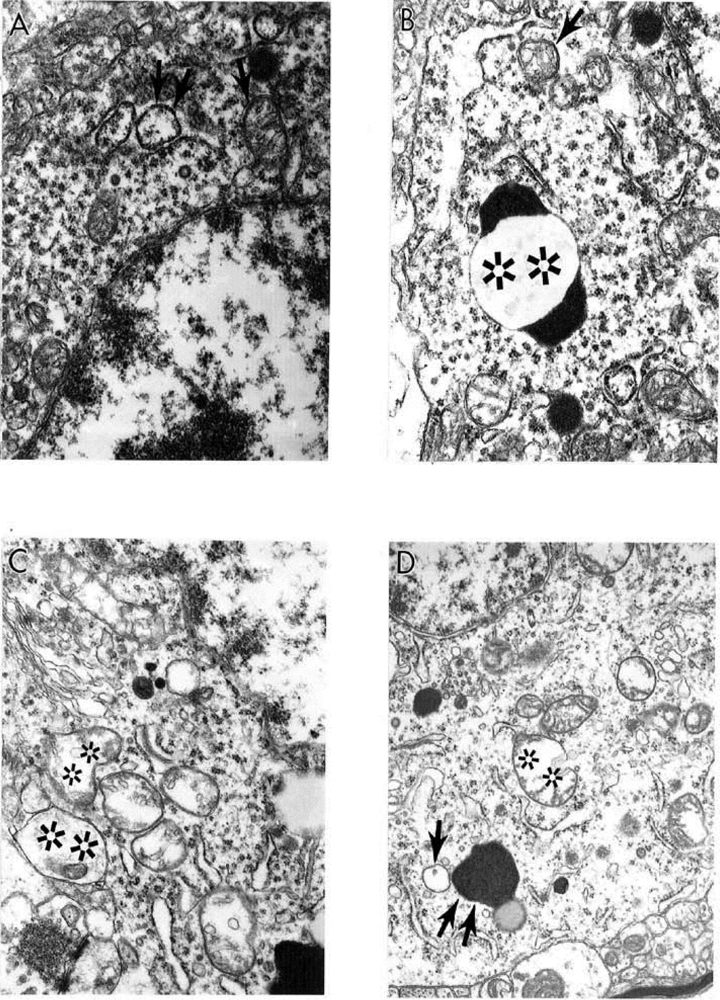

6.2. Cerebrovascular Lesions Observed During Ischemia/Reperfusion Induced Oxidative Stress